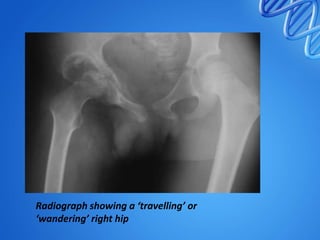

• 4. Advanced arthritis with subluxation /

dislocation :

• Furhter destruction of acetabulum , head ,

capsule and ligaments.

• Gross restriction of ROM

• Head – upwards and posteriorly

• Wandering / migrating acetabulum

• Mortle & pestle appearance

• Reduced joint space

Radiograph showing a ‘travelling’ or

‘wandering’ right hip